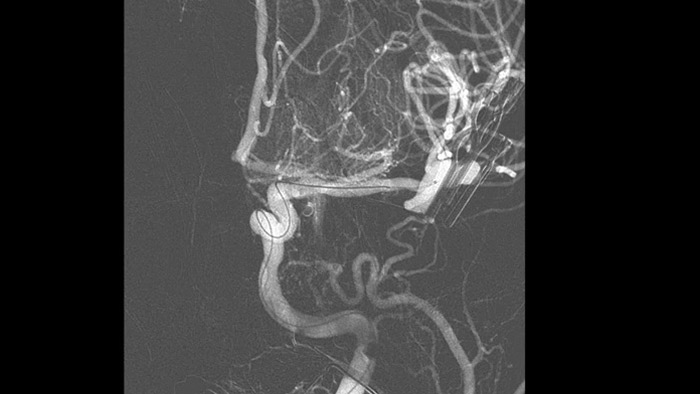

SmartCT Angio fournit une vue volumétrique en quelques secondes pour faciliter l’évaluation de l’emplacement, de la taille, du cou et de la gravité de l’anévrisme pour la planification du traitement. Les volumes 3D sont visualisés avec une résolution spatiale élevée et une compensation automatique des mouvements du patient.